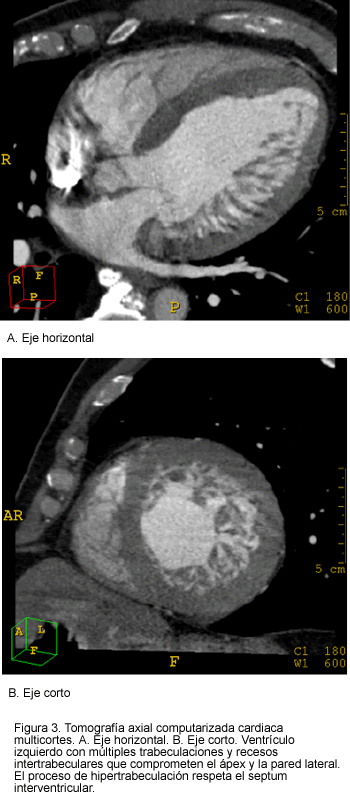

El electrocardiograma reveló ritmo sinusal, aumento del automatismo ventricular y bloqueo completo de rama izquierda. La radiografía de tórax evidenció un índice cardiotorácico aumentado (0,60) y leve redistribución del flujo sanguíneo pulmonar hacia los vértices pulmonares. La angiografía coronaria no reveló lesiones coronarias angiográficamente significativas y se informó como arteriografía coronaria normal. El ecocardiograma transtorácico mostró dilatación moderada del ventrículo izquierdo (diámetro diastólico de 63 mm, diámetro sistólico de 50 mm), hipertrofia ventricular izquierda (índice de masa miocárdica de 291 g/m2), hipocinesia global del ventrículo izquierdo con disminución significativa de la función sistólica (fracción de expulsión de 30%), y signos de disfunción diastólica por trastornos de la relajación (Doppler válvula mitral: onda E de 83 cm/s, onda A de 121 cm/s, tiempo de desaceleración de 245 ms) e hipertensión arterial pulmonar (presión sistólica de 50 mm Hg). El ventrículo izquierdo era hipertrófico, con abundantes trabeculaciones y recesos intertrabeculares profundos a nivel del ápex y de las paredes posteroinferior y lateral (Figura 1). El septum interventricular estaba hipertrófico, pero sin trabeculaciones y sin recesos intertrabeculares. Un ecocardiograma con infusión de contraste (microesferas de lípido perflutrén, Definity®) mostró de nuevo las trabeculaciones y el contraste opacificando los recesos intertrabeculares (Figura 2). Los hallazgos ecocardiográficos fueron compatibles con el diagnóstico de miocardiopatía del tipo VINC. Para corroborar estos hallazgos se realizó tomografía computarizada multidetector de 16 canales y angiorresonancia cardiacas, las cuales demostraron nuevamente los signos de no compactación del ventrículo izquierdo, con gran número de trabeculaciones y recesos intertrabeculares a nivel de los mismos segmentos informados en el estudio ecocardiográfico (Figura 3). La evolución del paciente ha sido aceptable, está en clase funcional I de la NYHA y actualmente recibe tratamiento con captopril, furosemida, glibenclamida, metformina, lovastatina y ácido acetilsalicílico.

El diagnóstico de VINC usualmente se realiza por ecocardiografía transtorácica, imagen de resonancia magnética y tomografía computarizada multidetector (1, 2, 21, 22). La ecocardiografía con contraste puede ser útil cuando la ecocardiografía estándar demuestra problemas de ventana acústica o cuando el diagnóstico es dudoso (23). Con frecuencia, los signos de hipertrabeculación y los recesos intertrabeculares pasan desapercibidos durante el examen ecocardiográfico y se confunden con otros tipos de miocardiopatías, como miocardiopatía dilatada, hipertrófica, hipertrófica variedad apical y restrictiva; fibrosis endomiocárdica y fibroelastosis endocárdica.